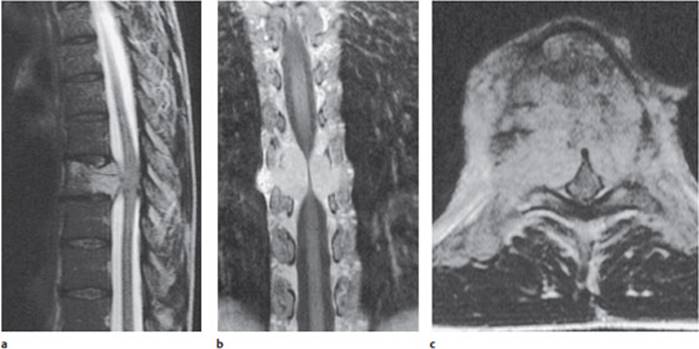

Fig. 4.2 Chordoma of the T7 vertebral body in a 48-year-old woman. a The spinal cord is posteriorly displaced and compressed. b An image in the frontal plane after the administration of contrast medium shows the tumor compressing the spinal cord from both sides, c At the level of the tumor, the subarachnoid space is completely obliterated by tumor.